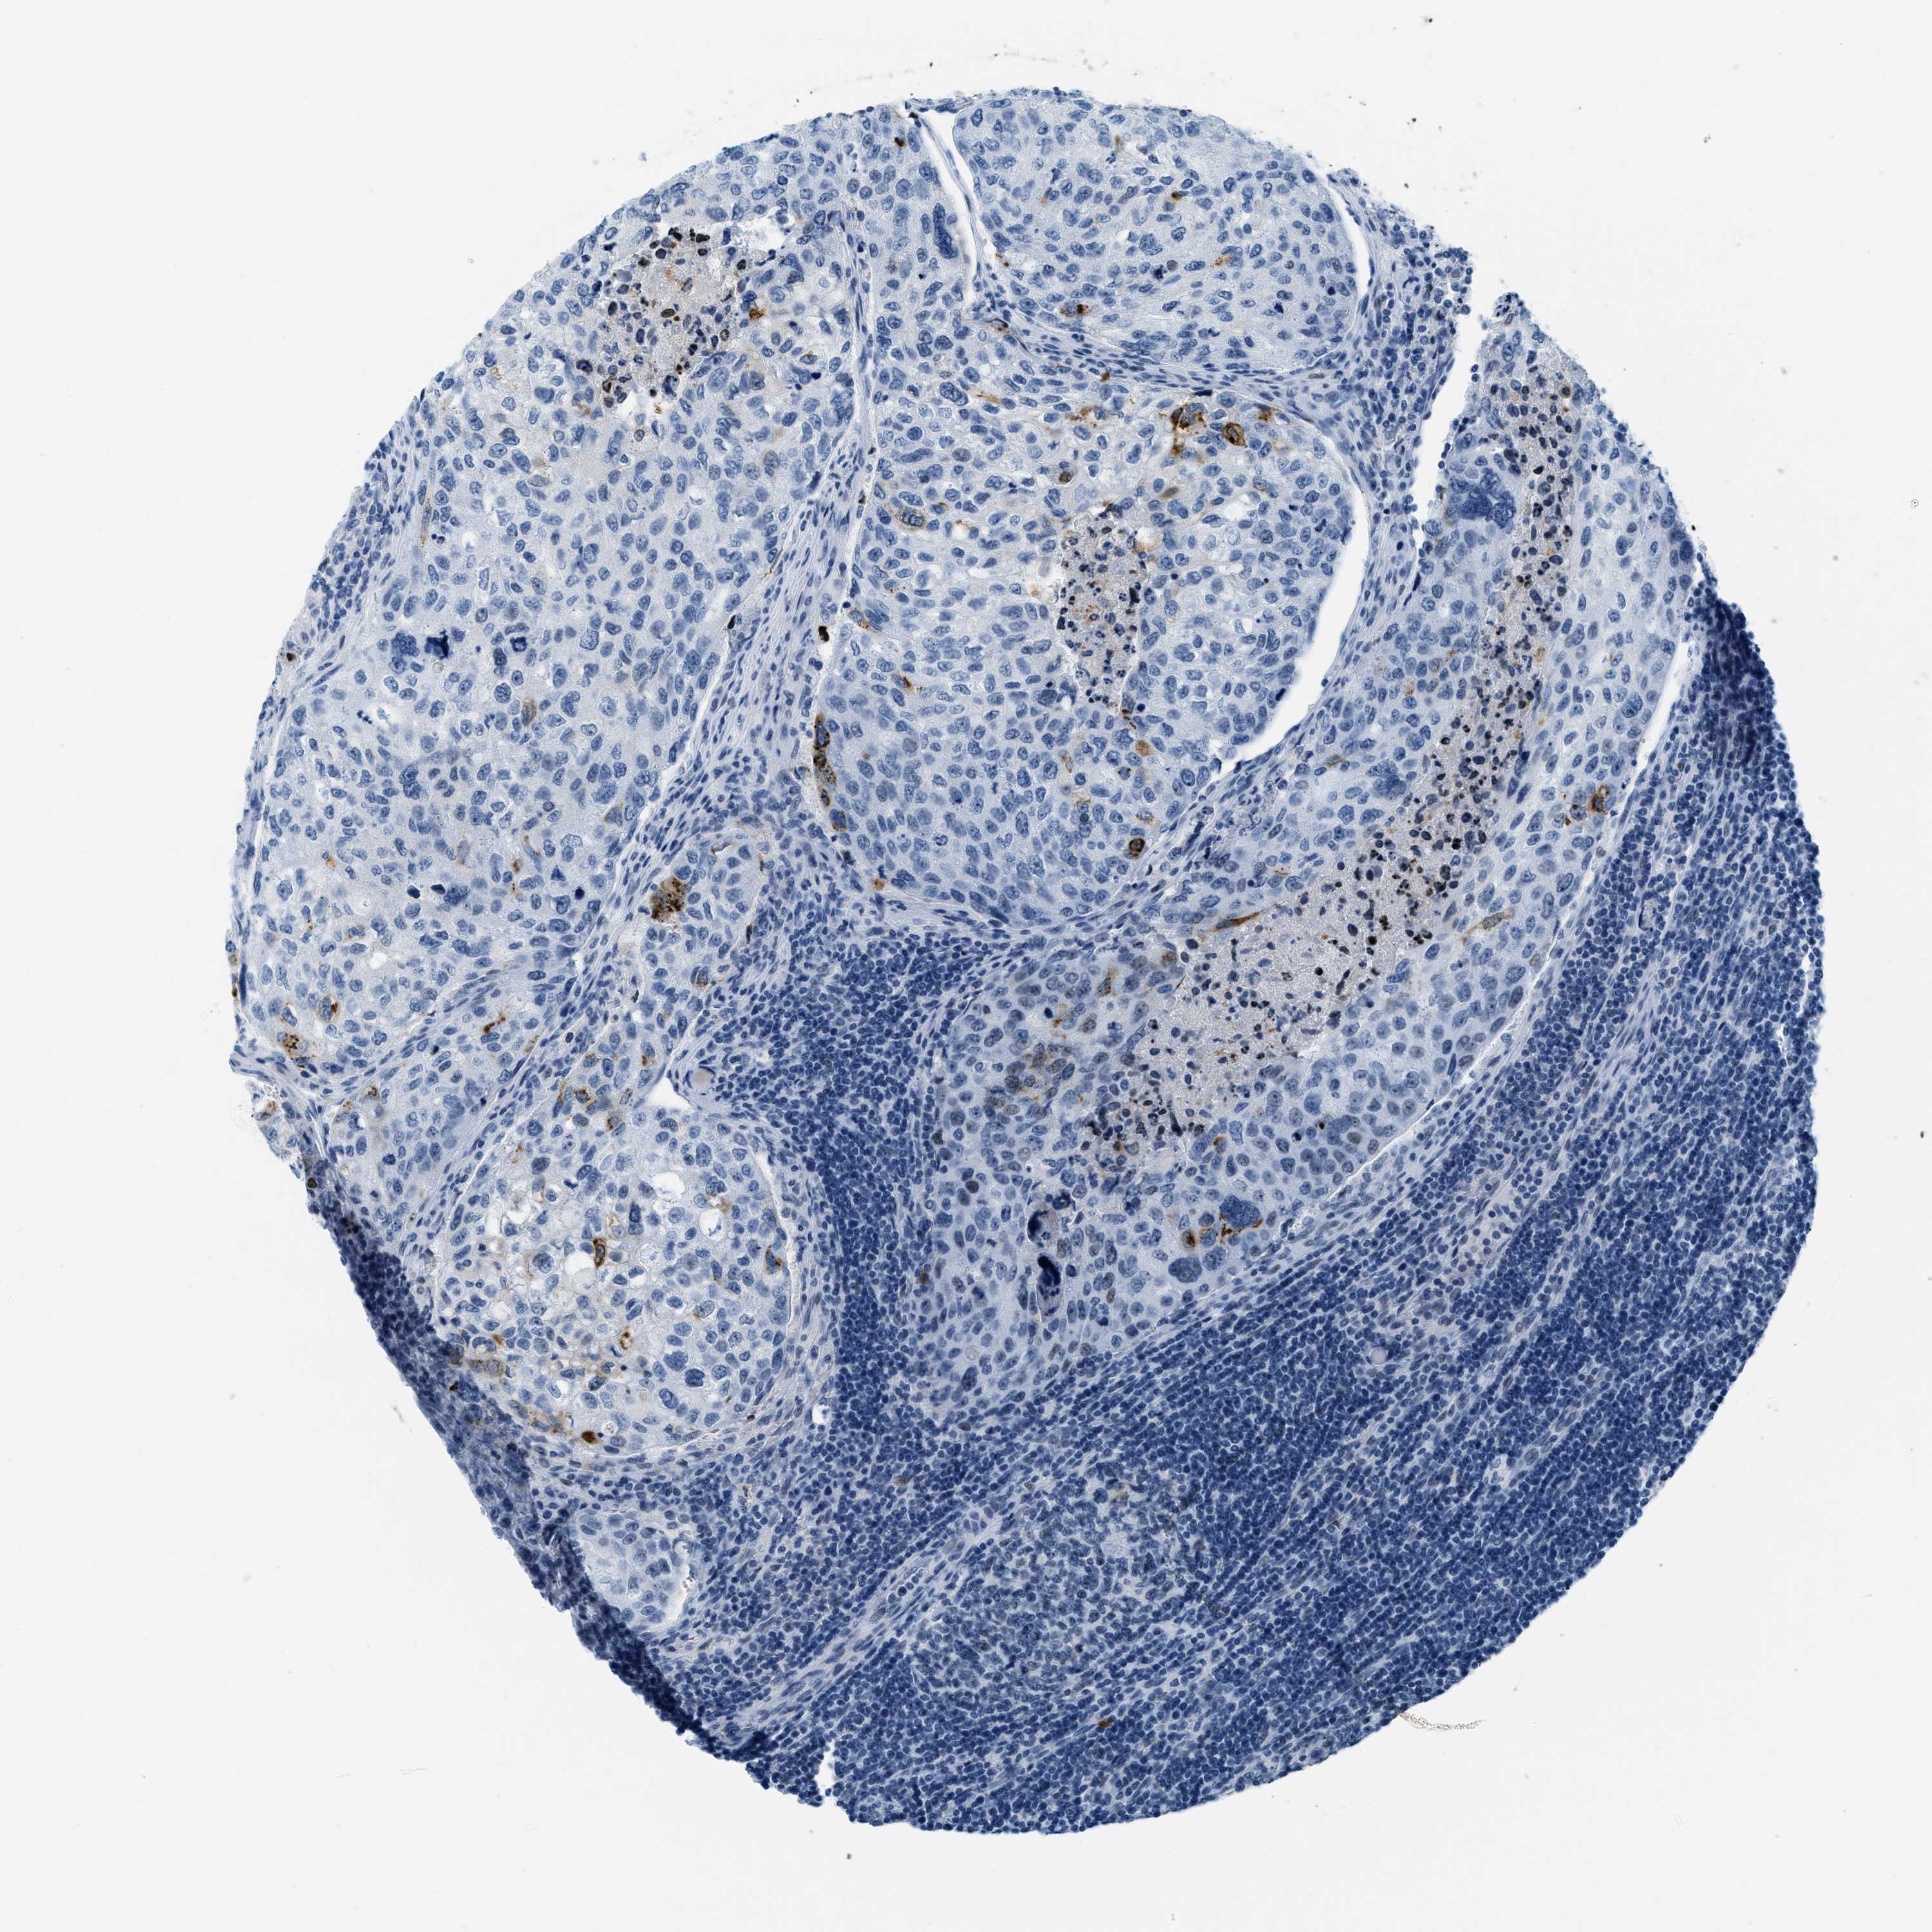

UROTHELIAL CANCER - Protein expressioni

A mouse-over function shows sample information and annotation data. Click on an image to view it in a full screen mode. Samples can be filtered based on level of antibody staining by selecting one or several of the following categories: high, medium, low and not detected. The assay and annotation is described here.

Note that samples used for immunohistochemistry by the Human Protein Atlas do not correspond to samples in the TCGA dataset.

Antibody stainingi

Antibody staining in the annotated cell types in the current human tissue is reported as not detected, low, medium, or high, based on conventional immunohistochemistry profiling in selected tissues. This score is based on the combination of the staining intensity and fraction of stained cells.

Each image is clickable and will lead to virtual microscopy that enables deeper exploration of all samples and also displays staining intensity scores, fraction scores and subcellular localization as well as patient and tissue information for each sample.

Antibody HPA015236

Staining

High

Medium

Low

Not detected

Intensity

Strong

Moderate

Weak

Negative

Quantity

>75%

75%-25%

<25%

None

Location

Urothelial carcinoma, Low grade

Urothelial carcinoma, High grade